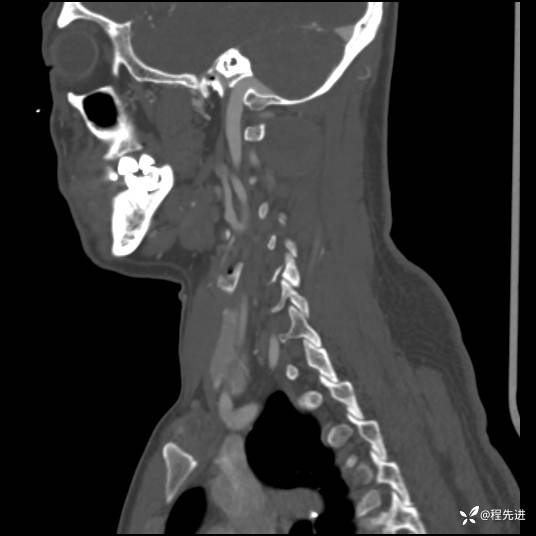

CT平扫+增强:

现病史:患者3个月前低头工作后感颈部疼痛,隐痛,活动颈部后稍好转,无上肢麻木不适,无肢体活动障碍,无头晕头痛,3个月来疼痛反复发作

患者性别:男

患者年龄:43岁

主诉:颈部疼痛3个月